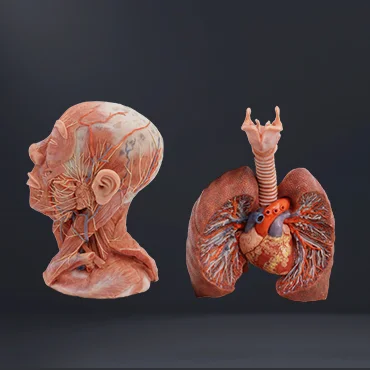

Zhengzhou Meiwo Science & Technology Co., Ltd established in 2009, is a comprehensive technology enterprise for medical education integrating R&D, production and sales. Meiwo Science has independent specimen production workshops and model production workshops covering an area of 10,000 square meters. Meiwo main products involve plastinated animal specimens, soft silicone anatomy models, high simulation soft anatomy models, human & animal anatomy softwares, 3D digital human specimen, biological microscope slides, animal skeletons, etc.

What we offer: